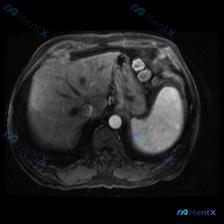

最近看到一个腹部MRI的病例,觉得在鉴别诊断上挺有代表性的,整理一下资料和思路跟大家分享。 先看影像资料(轴位T1序列) - 肝脏、胰腺、胆道、双肾及腹膜后:都没看到明显异常信号或占位,肝内血管、胆总管也不宽,腹膜后没见肿大淋巴结。 - 脾脏(重点):形态大致正常,但实质内有一个边界比较清楚的异常信...

整理了一份腹部MRI-T1加权轴位平扫的病例资料,同时结合了完整的分析思路,分享出来一起讨论。 核心影像表现 1. 脾脏:体积增大,内部可见多发明显的低信号结节影/斑片影,呈弥漫性分布,边界相对模糊 2. 肝脏:肝实质信号欠均匀,可见多发斑点状、类圆形低信号影散在分布 3. 右侧肾上腺区:可见类圆形...